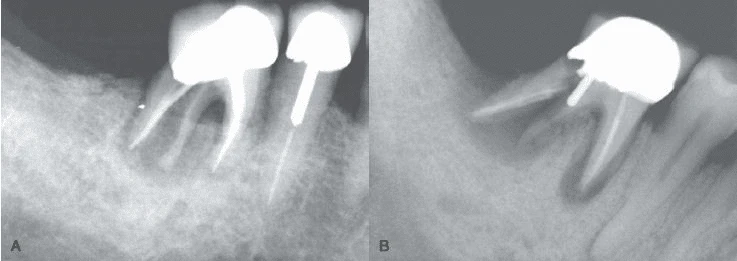

Hình 10. Nứt dọc chân răng dẫn đến chia đôi chân răng, điều này có thể phát hiện dược trên X quang

Hình 11. Mặc dù nứt dọc chân răng không phải lúc nào cũng thấy được trên X quang nhưng với một góc chụp đúng thì có thể quan sát rõ đường nứt.